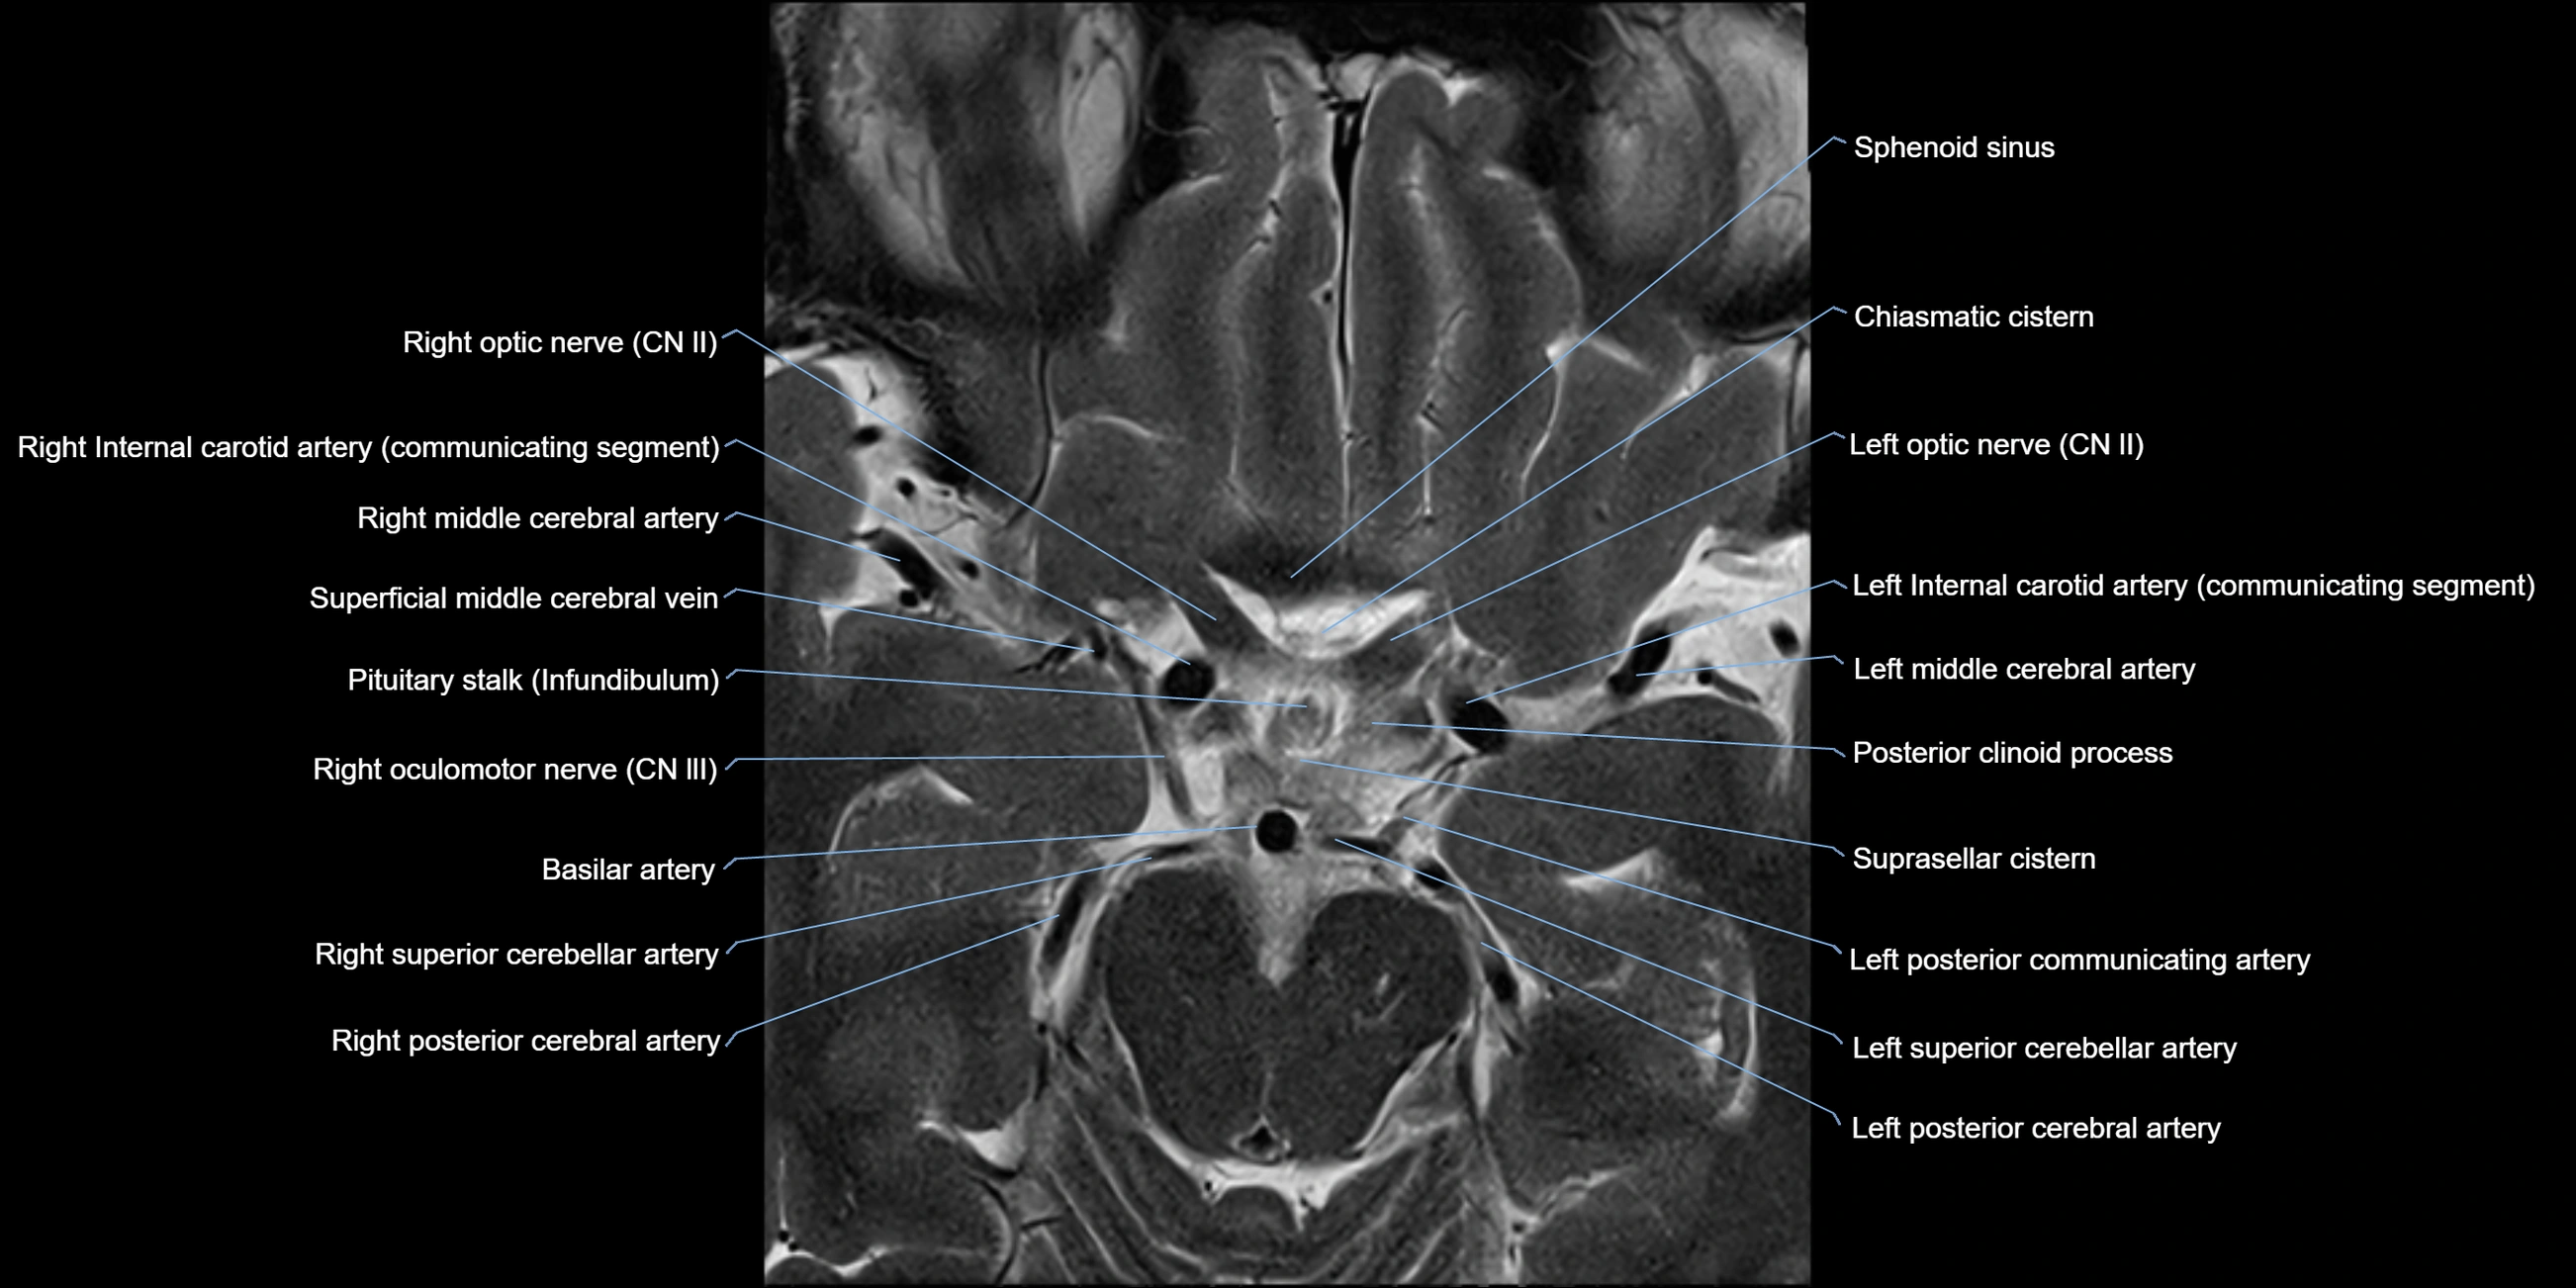

MRI Appearance

The abducens nerve is a small, thin, linear structure

Best visualized on high-resolution T2-weighted 3D MRI sequences (e.g., FIESTA or CISS)

Seen as a hypointense (dark) line running from the brainstem at the pontomedullary junction, traversing the prepontine cistern, and entering Dorello’s canal under the petrosphenoidal ligament, then into the cavernous sinus, and finally the orbit

May be challenging to visualize in standard MRI due to its small size

Pathology may be inferred by absence, displacement, or enhancement of the nerve

MRI images